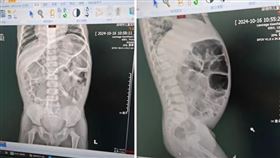

新竹男20天沒排便 宿便頂到心臟

新竹一名58歲陳性男子日前因腹脹就醫,醫師初步以肛門...